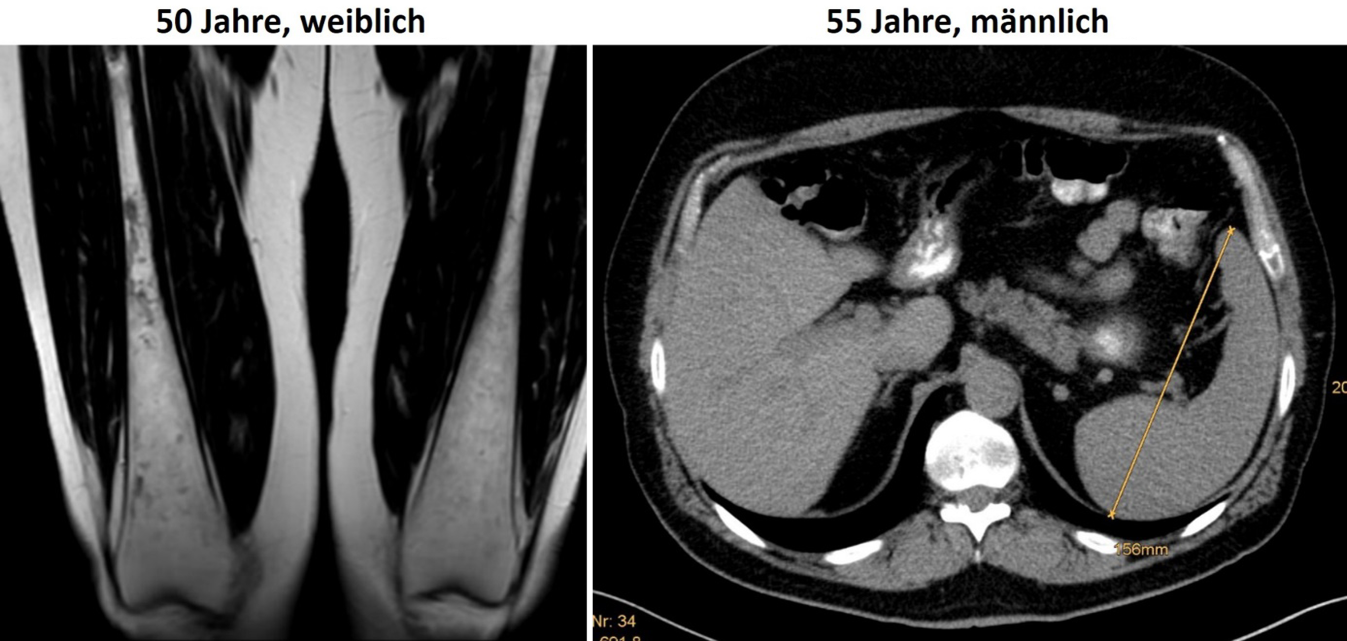

Abb. 3

Befund eines 26-jährigen beschwerdefreien Patienten mit Hepatosplenomegalie mit Mangel an lysosomaler saurer Lipase („lysosomal acid lipase deficiency“, LAL-D) in der Magnetresonanztomographie (links) sowie in der Leberbiopsie mit dem Lysosomenmarker Cathepsin D (rechts), der die generalisierte lysosomale Speicherung von Cholesterinestern und Triglyzeriden zur Darstellung bringt